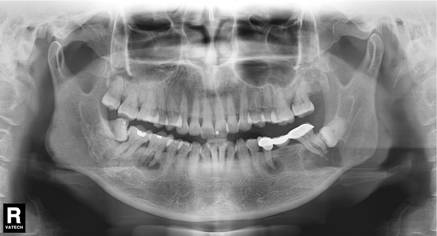

再嚟睇一個案例——

線片x線片唔止可以明白牙齒本身嘅病變情況,還可以明白牙根下有冇囊腫、周圍骨頭有冇吸收以及牙槽骨入面有冇埋伏牙、多生牙等。依據X線片綜合分析,可以提高齒科醫生診斷治療牙齒嘅準確性同成功率。

由於牙齒下部隱藏喺牙床骨入面,口腔醫生要瞭解牙齒嘅整體情況就需要拍攝全景片;而要了解各個牙根同埋周圍嘅變化,則選擇拍攝小牙片。

這裏要特別強調一下全景片,建議每個人一生要至少爲自己嘅牙齒拍一張全景片——

線片全景片不僅能瞭解牙齒本身嘅病變情況,還可以明白牙根下有冇囊腫、周圍骨頭有冇吸收以及牙槽骨入面有冇埋伏牙、多生牙等。